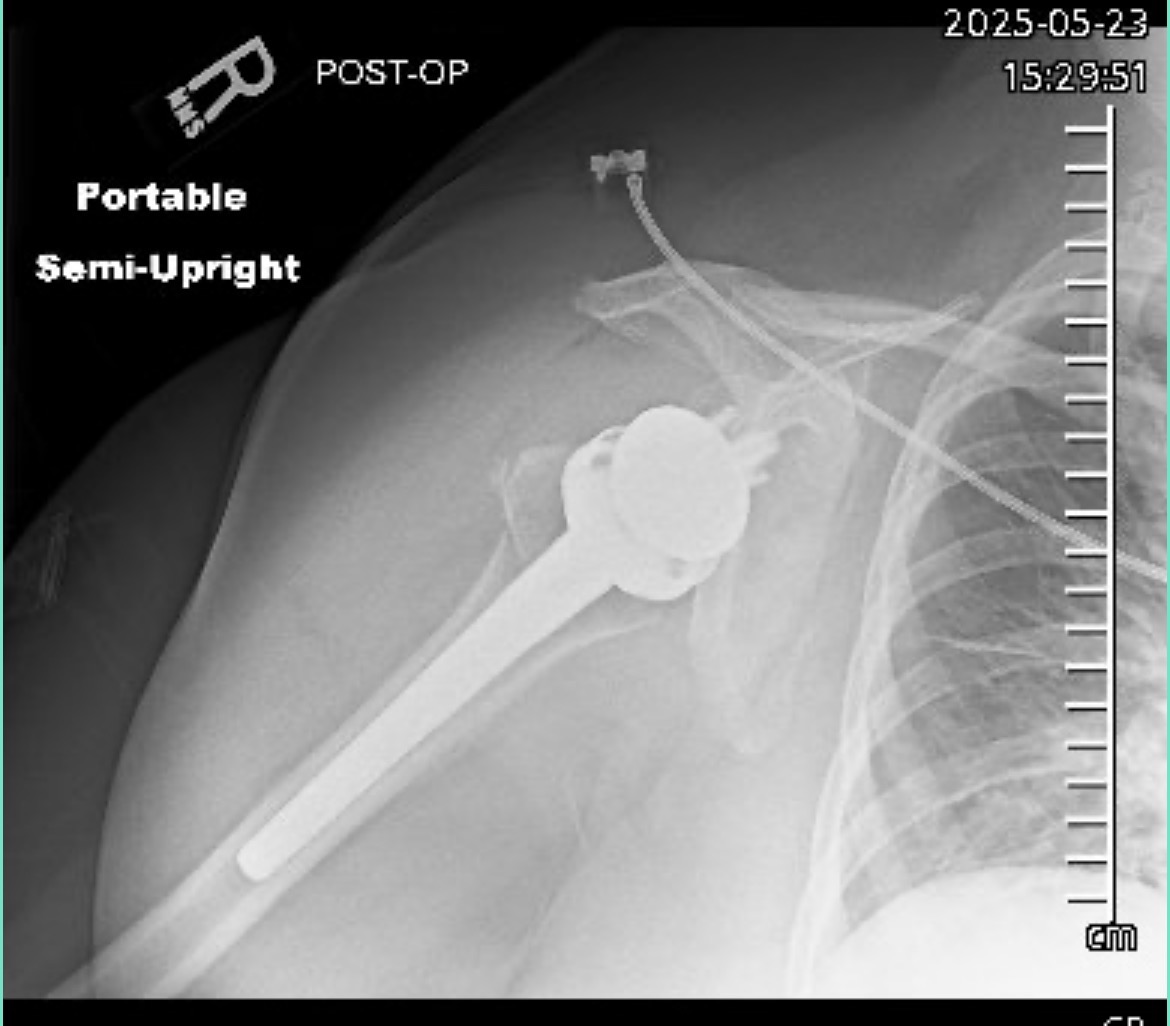

Update: I have had surgery. Now it is a waiting game.

Last Friday morning, what started as a normal day took an unexpected and devastating turn. While walking into a local shop for coffee, I had a fall that resulted in a broken shoulder. I've since learned that the break is severe – into three pieces, with the top part completely detached. I’ve met with an orthopedist to determine the best course of action. The doctor has presented two difficult options:

Reversal shoulder replacement surgery: This comes with a higher risk of complications and may not fully restore the mobility I need.

My choice is surgery.